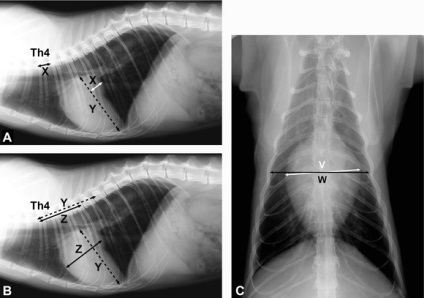

Găsirea murmur cardiac și aritmii cardiace, specialist veterinar, de obicei numește radiografia toracică, electrocardiograma și ecocardiografie a inimii.

Examinarea cu raze X poate detecta nu numai o creștere a ventriculului stâng și atrium, dar, de asemenea, pentru a identifica revărsat pleural. ECG inima relevă încălcări în activitatea sa, în 70% dintre pacienții cu pisici Cardiomiopatia hipertrofică.

Metoda cea mai informativa de diagnostic și diferențiere față de alte boli cu cardiomiopatie este corp cu ultrasunete. Metoda permite estimarea grosimii peretelui inimii, diametrul găurii aortei. Folosind medicul veterinar inima cu ultrasunete poate evalua dimensiunea și forma fluxului sanguin atriale în camerele inimii, pentru a detecta trombi.